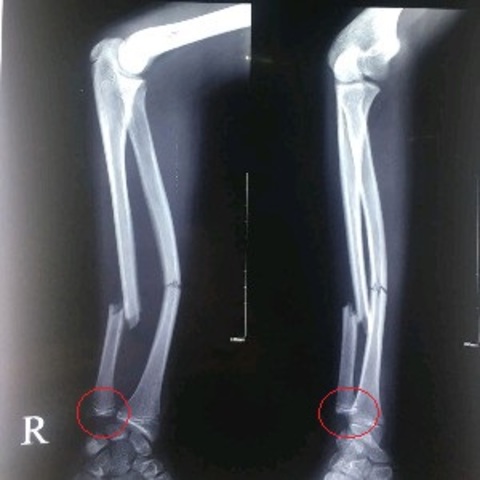

ini fto rontgen saat datang ke UGD stelah 3 minggu post KLLnya

Kalo menurut hemat saya, pasien tersebut tetap harus melakukan reduksi internal dok. Karena seperti terlihat dari xray-nya, tulang sangat displaced dan fraktur sangat tidak stabil, kalo tidak dilakukan re-allignment tidak akan union dok. Dan kalo tidak diimobilisasi, tidak akan sembuh dok.

Perhatikan bagian yang dilingkari merah pada foto. Terlihat jelas dislokasi ulnar head yang menunjukkan bahwa segmen distal tulang yang patah melayang dan tidak tersambung ke manapun. Hal ini merupakan concern utama untuk merujuk pasien ke ortopedi. Sisanya sih sama dengan dokter Qintha, ciptakan urgensi untuk rujukan dengan mengedukasi pasien bahwa jika tidak dirujuk, tangannya tidak akan sembuh.